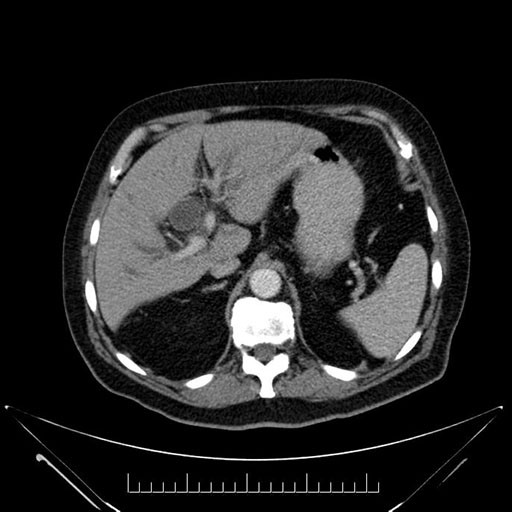

Imaging Analysis

Look through the patient's CT scan to identify any areas of concern for the necessary procedure.

Based on your CT findings, which issue(s) would give reason for "planned slowing down moment(s)" in this case?

Considering a standard Whipple procedure, what step(s) of the operation would you do differently in this case?